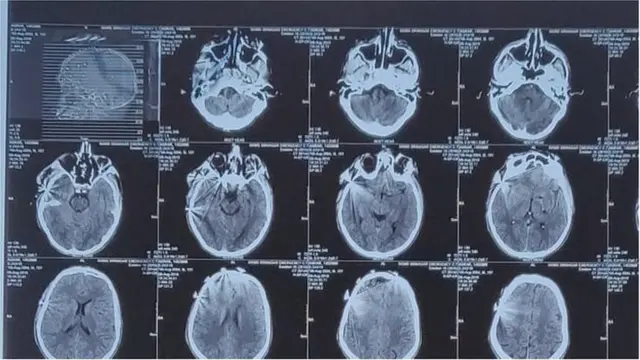

6 ऑगस्ट रोजी असरार अहमद खान या 17 वर्षीय मुलाला रस्त्याच्या कडेला असताना दुखापत झाली. रुग्णालयात दाखल केल्यानंतर चार आठवड्यांनी हॉस्पिटलमध्ये त्याचा मृत्यू झाला.

वैद्यकीय अहवालानुसार, असरारचा मृत्यू पॅलेटगनच्या गोळ्यांमुळं आणि अश्रुधुराचे डब्यांच्या स्फोटामुळं झाला. मात्र, काश्मीरमधील भारताचे वरिष्ठ लष्करी अधिकारी लेफ्टनंट जनरल केजेएस धिल्लो यांच्या म्हणण्यानुसार, काश्मिरी आंदोलकांनी भारतीय सैन्यावर फेकलेल्या दगडफेकीत असरारच्या मृत्यू झाला.